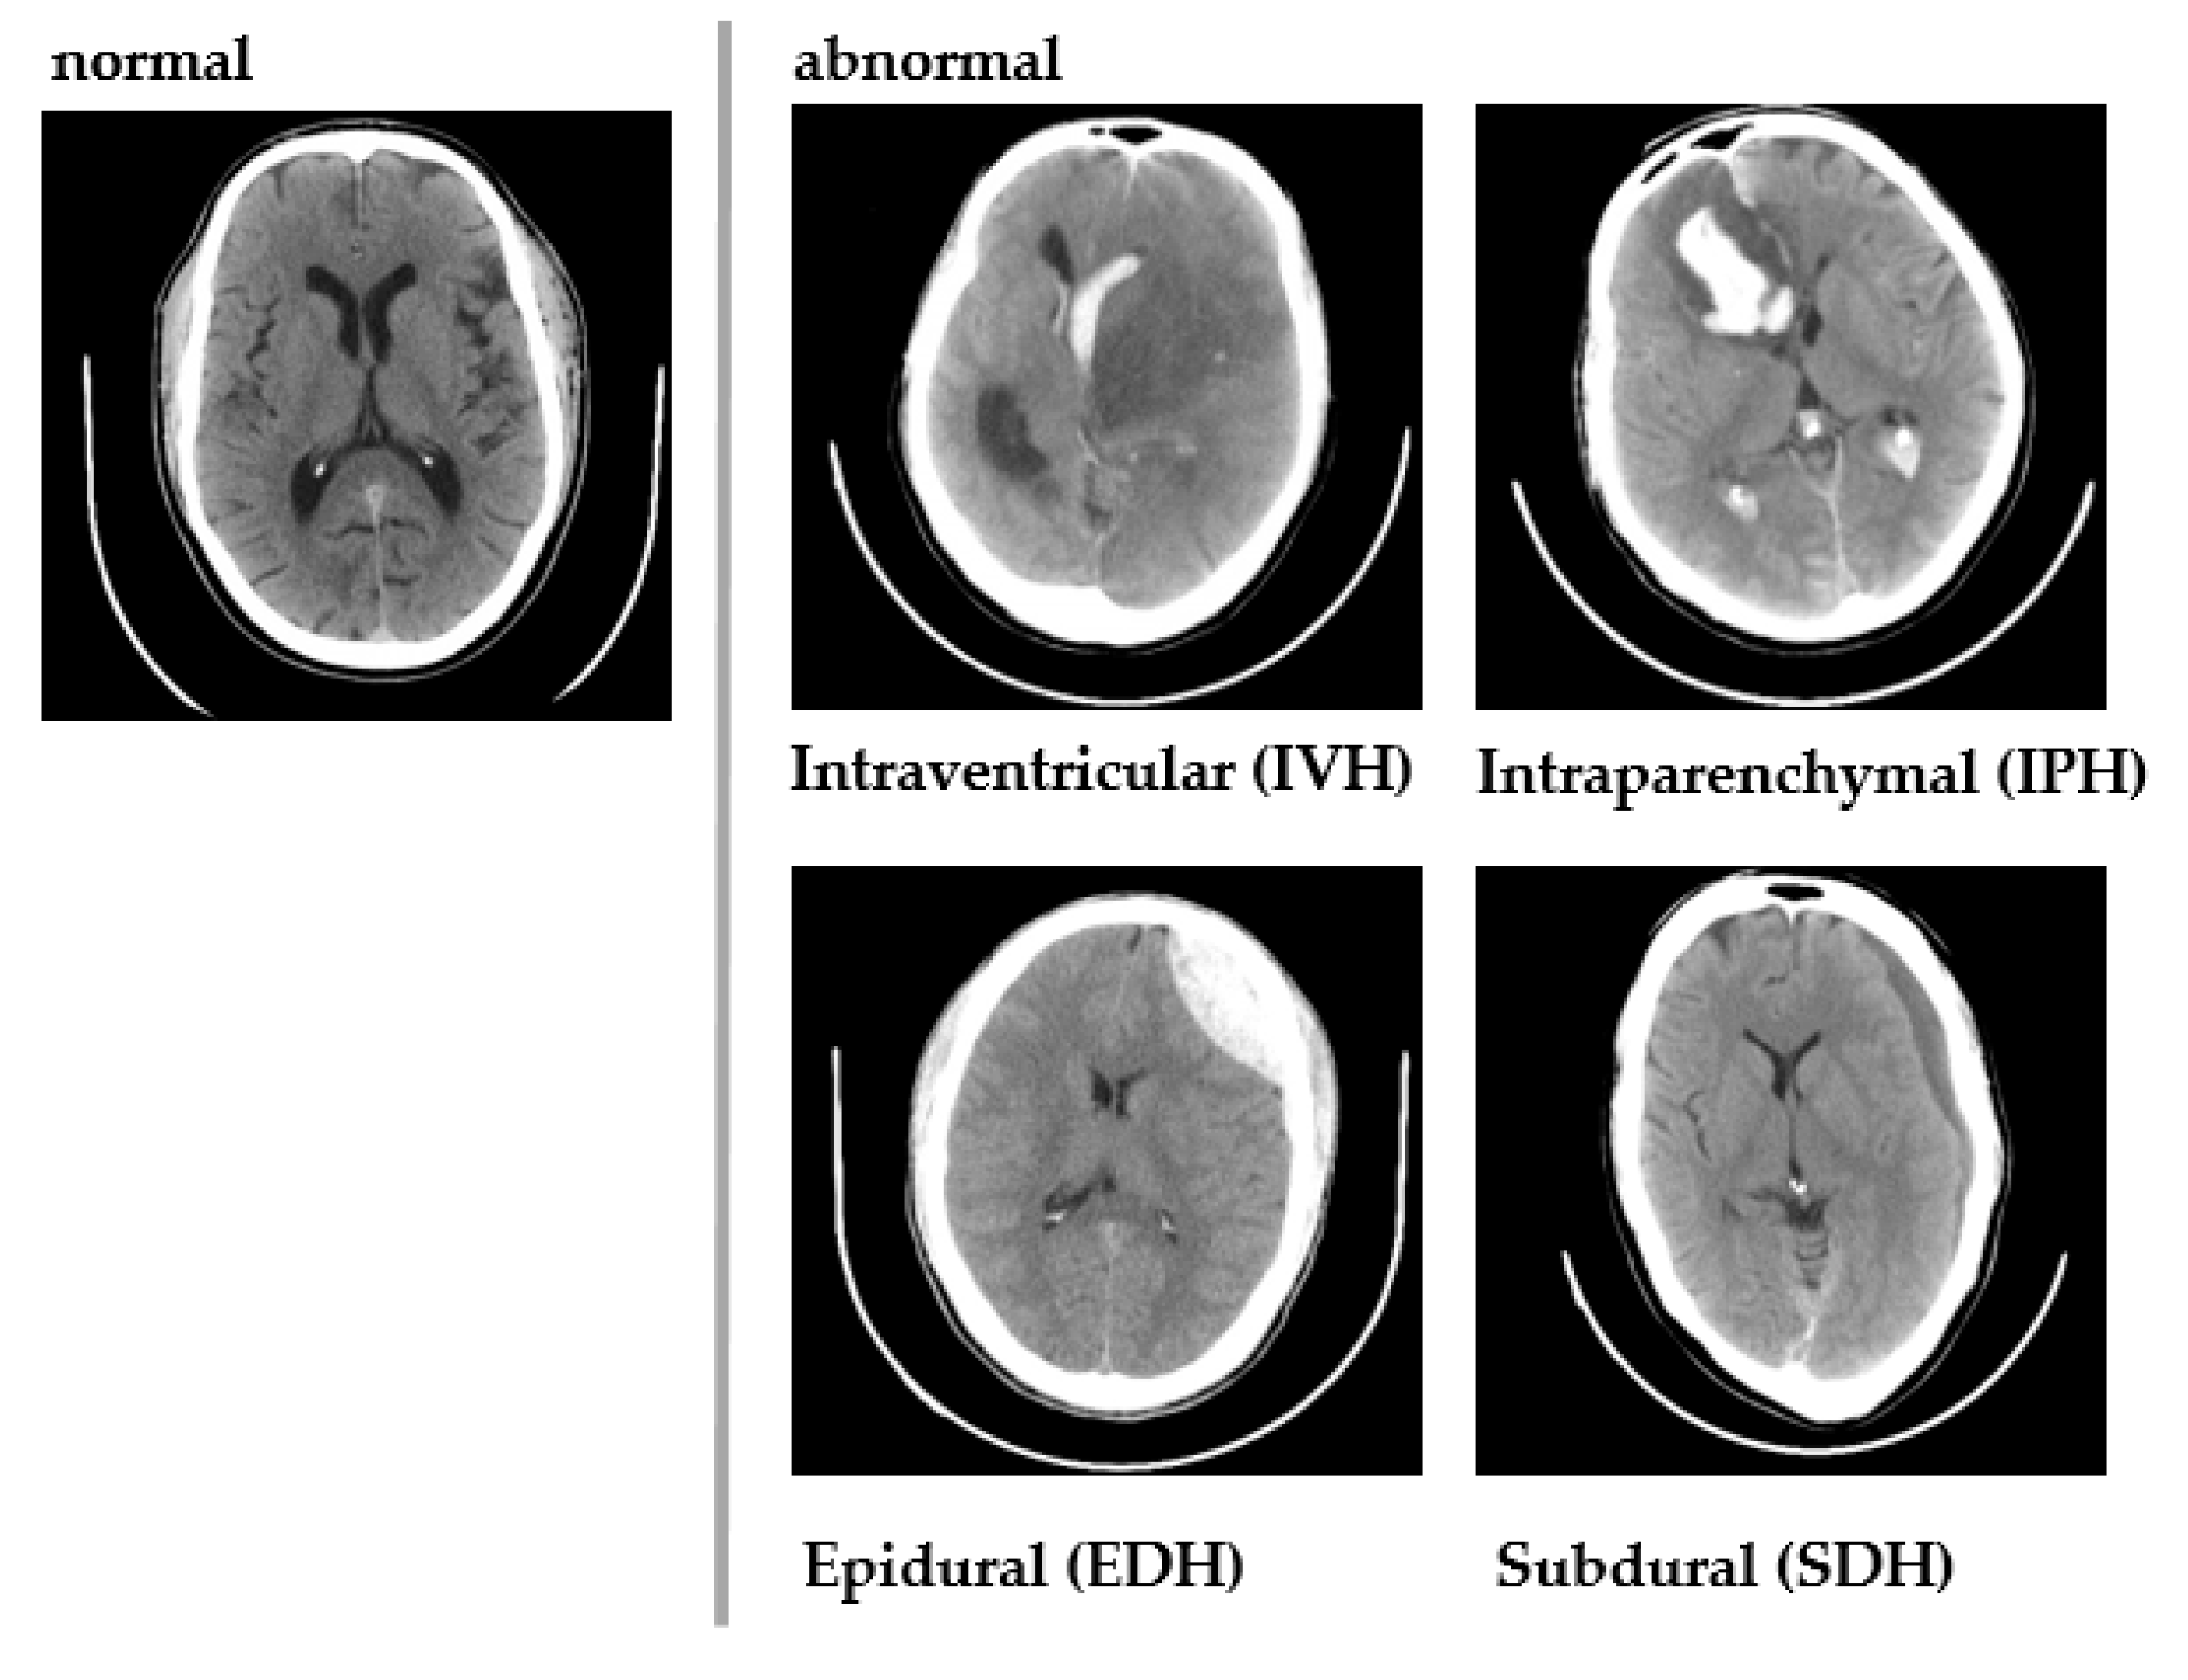

Chilamkurthy et al. [36] created a diverse CQ500 dataset comprised of 491 brain CT scans, which were collected batch-wise from different radiology units and pooled by the Centre for Advanced Research in Images, Neurosciences and Genomics (CARING), New Delhi, India. Each CT scan was annotated by three independent radiologists for the presence or absence of (i) ICH and its five types, ICH age, and affected brain hemisphere, (ii) midline shift, and (iii) calvarial fractures. Figure 4 shows a sample of normal and abnormal images included in the dataset.

Figure 4.

Sample CT images from CQ500 dataset.